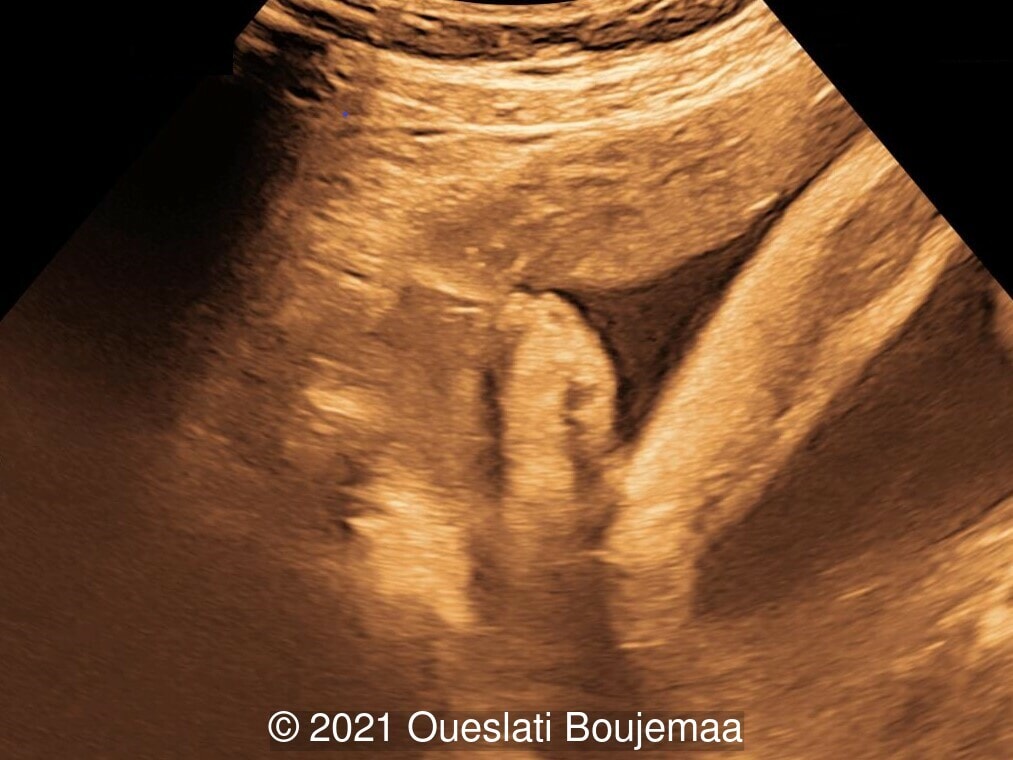

We present a case of Trisomy 18.

Our ultrasound demonstrated the following findings:

- Fetal growth restriction (5th percentile)

- Microcephaly (head circumference <3rd percentile)

- Cerebellar hypoplasia

- Enlarged cisterna magna (cerebellomedullary cistern) with Blake's pouch cyst

- Facial dysmorphism with retrognathia

- Cardiac malformation with ventricular septal defect and linear insertion of the atrioventricular valves

- Lower extremities show “sandal gap” (wider gap between the first and second toe), and rocker-bottom feet with prominent heels

Our initial concern was trisomy 18. An amniocentesis was performed and confirmed the diagnosis. A female neonate was delivered at 40 weeks gestation with a birthweight of 2100 grams. Physical examination confirmed the malformations of the extremities and facial dysmorphism. The infant was admitted to the hospital for respiratory distress. Postnatal echocardiography confirmed a ventricular septal defect and linear insertion of the atrioventricular valves. Additionally, there was an atrial septal defect. Postnatal karyotype confirmed Trisomy 18. The infant died at 3 months of age.